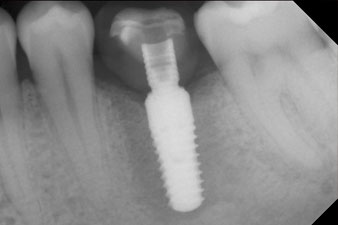

The implant was placed as planned after thorough removal of the granulation tissue (blueSky, bredent).

The torque used for the machine-driven placement was 43 Ncm. In addition, after screwing a measuring post (SmartPeg) specially matched to the implant, the ISQ value was measured with the probe of the W&H Osstell ISQ module.

This module is an optional extra for the W&H Implantmed and is docked to the implantology motor (see Fig. 11). The dimensionless ISQ value immediately after insertion was 64 orovestibular and 68 mesiodistal (maximum value = 100).

These values could have indicated open healing or even immediate restoration. Due to the insufficient crestal bone volume at the implant, the region was augmented with the bone chips collected during preparation of the implant bed and sutured to exclude saliva.

The final pictures show the screw-retained monolithic composite crown in place and the x-ray check (Fig. 9 and 10) (6).